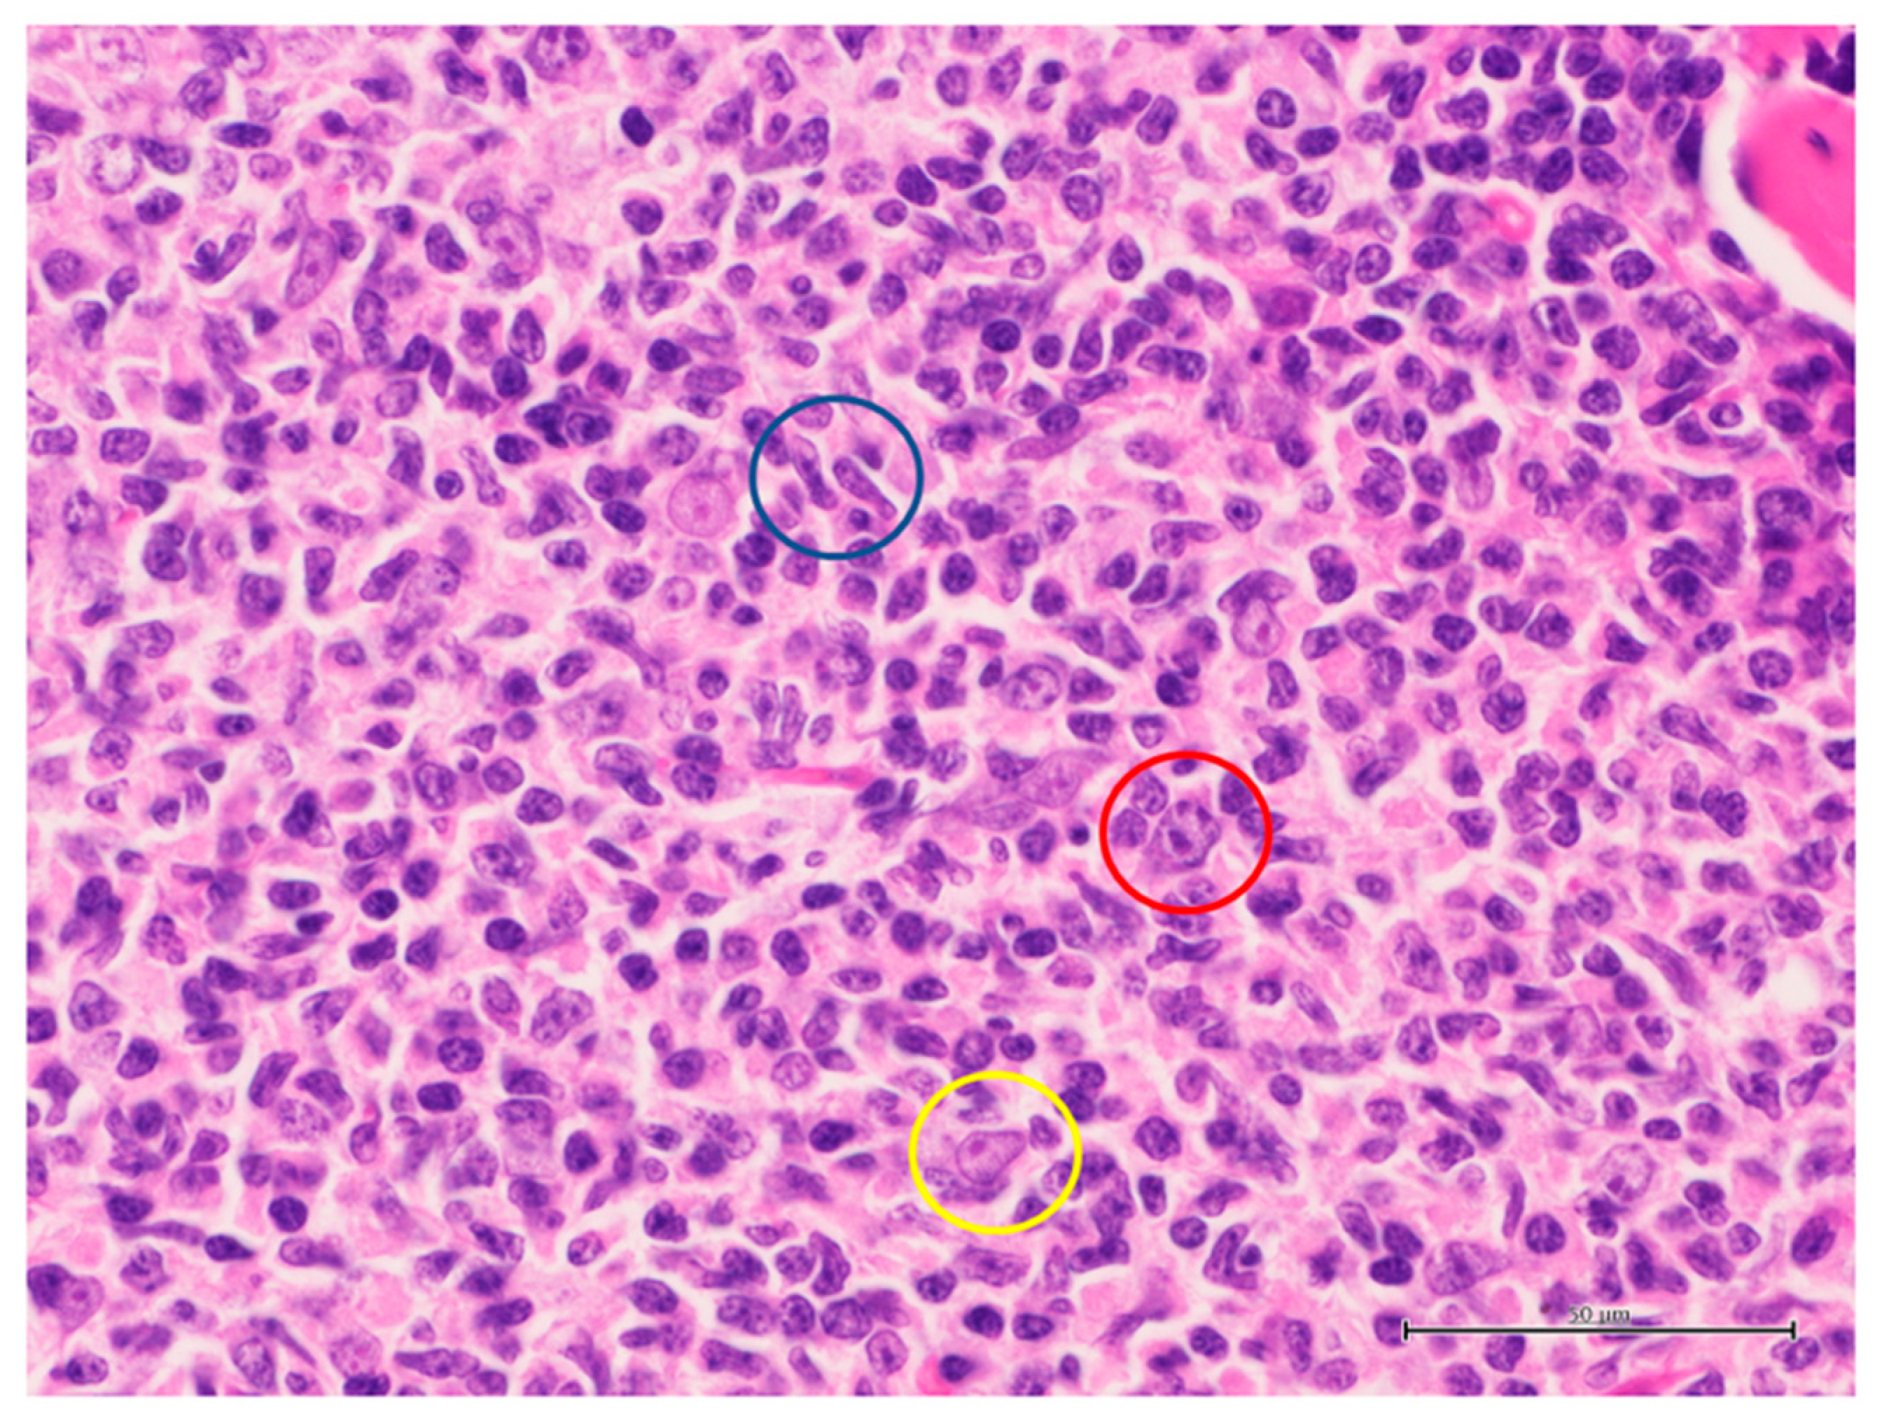

2.2. Histological Findings

3.2. Histological Findings

4.2. Histological Findings